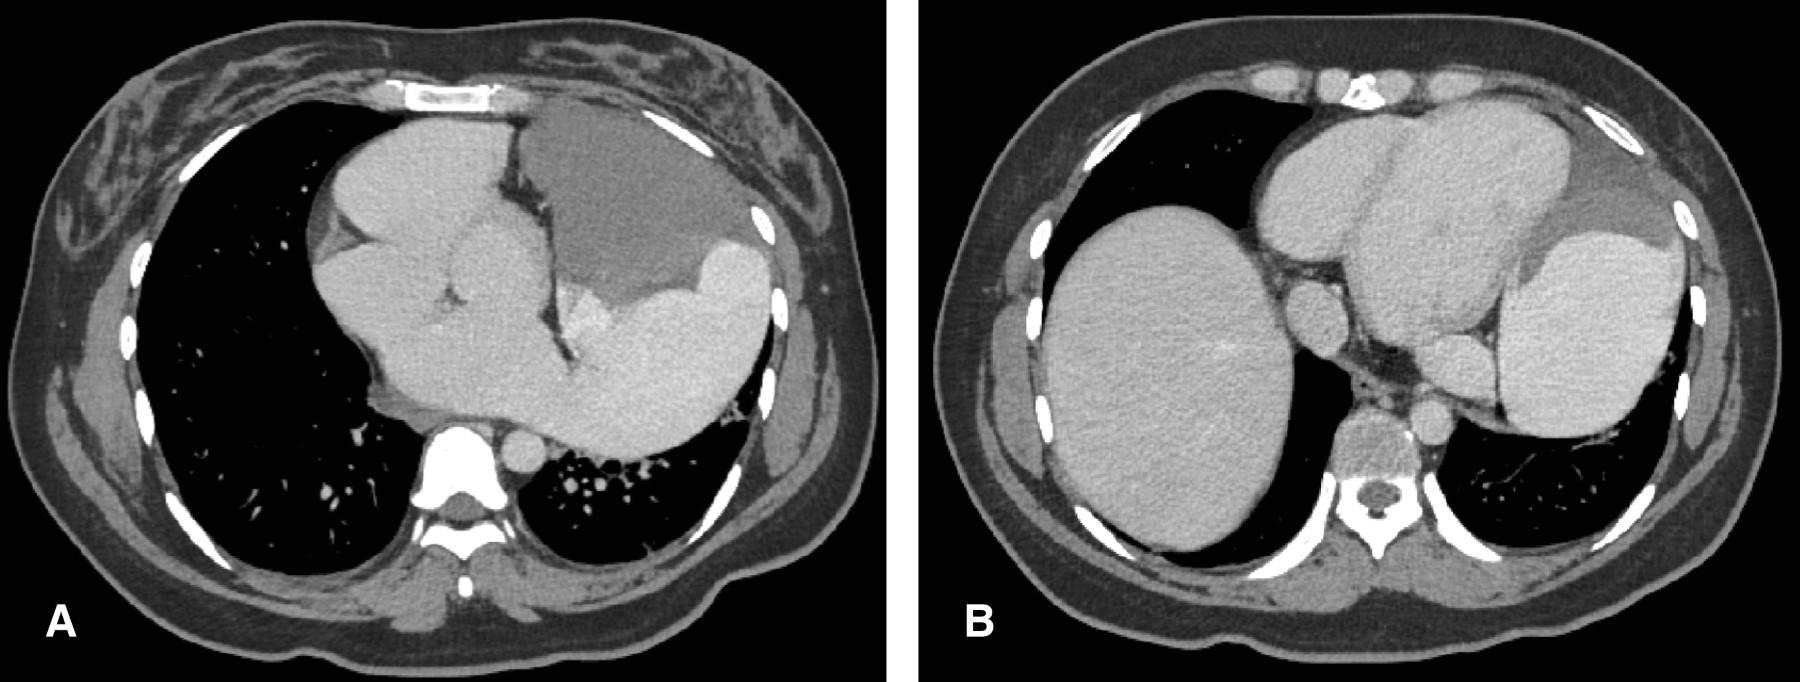

Aneurisma de la orejuela izquierda como causa de evento vascular isquémico: reporte de caso y revisión de la literatura

El aneurisma de la orejuela izquierda es una entidad rara, con pocos casos reportados en la literatura, pero con potenciales implicaciones clínicas significativas. Presentamos el caso de una paciente que debutó con evento vascular isquémico. La evaluación con estudios de imagen evidenció un aneurisma de la orejuela izquierda. Dado el alto riesgo embólico, se decidió el manejo quirúrgico mediante exclusión de la orejuela izquierda. La evolución postoperatoria fue favorable.

Figura 1